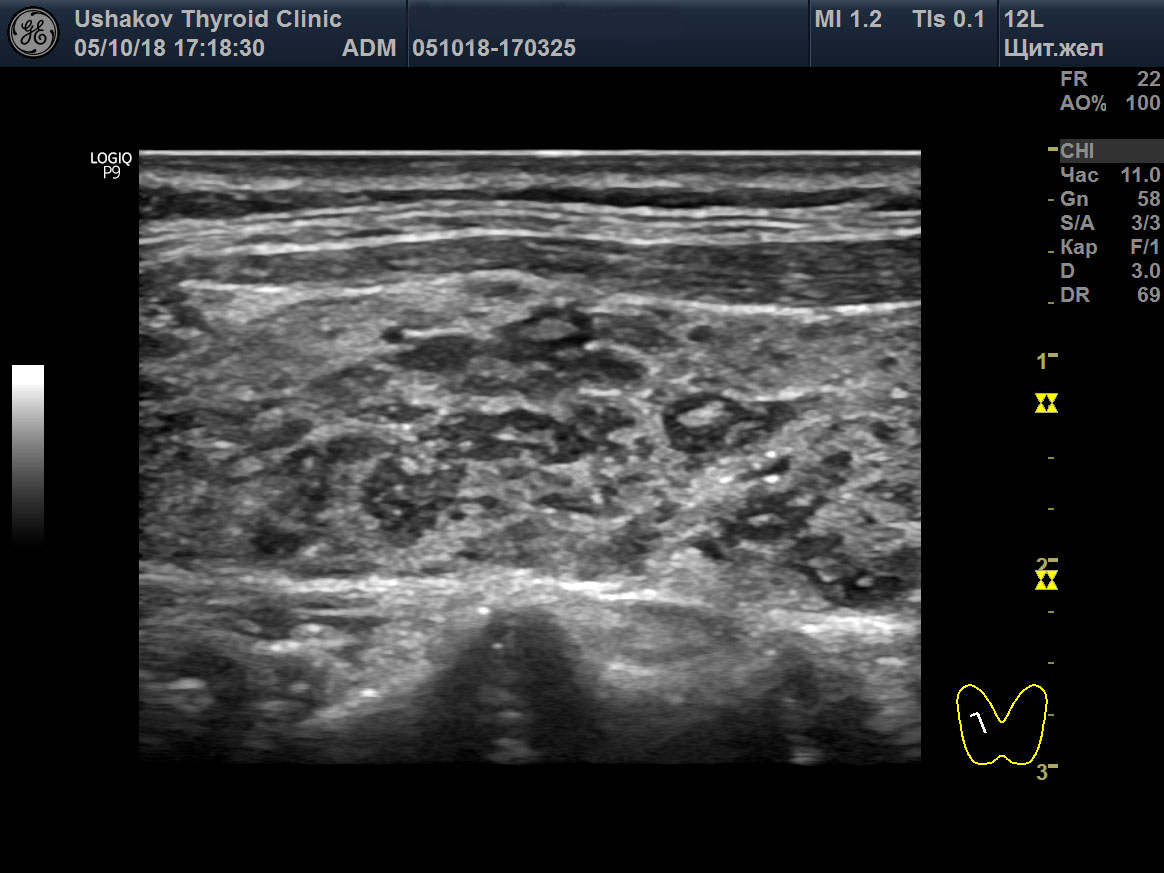

В последующем в дольке начинает происходить регенерация. Из стволовых клеток (или иначе) внутри лимфоидной ткани дольки появляется мелкий участок нормальной ткани щитовидной железы, который постепенно разрастается и заполняет объём дольки. Вместе с тем уменьшается количество лимфоидной ткани. При УЗИ эта фаза внутридольковой регенерации представляет собой разной величины гипер- или изоэхогенный участок внутри гипоэхогенной дольки (

рис. 2).

Рисунок 2 (начало) Правая доля ЩЖ пациентки 64 лет (поперечная, продольная проекции и увеличение; В-режим и ЭДК). Значительно выраженная внутридольковая регенерация в дольках с лимфоидной тканью. Фазы начальной и активной внутридольковой регенерации. Внутри гипоэхогенной (лимфоидной) ткани долек («лимфоидные дольки») определяются мелкие и крупные гипер- и изоэхогенные элементы регенерирующей ткани.